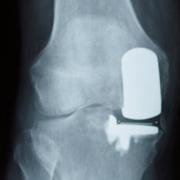

Patient not settling after unicondylar replacement.